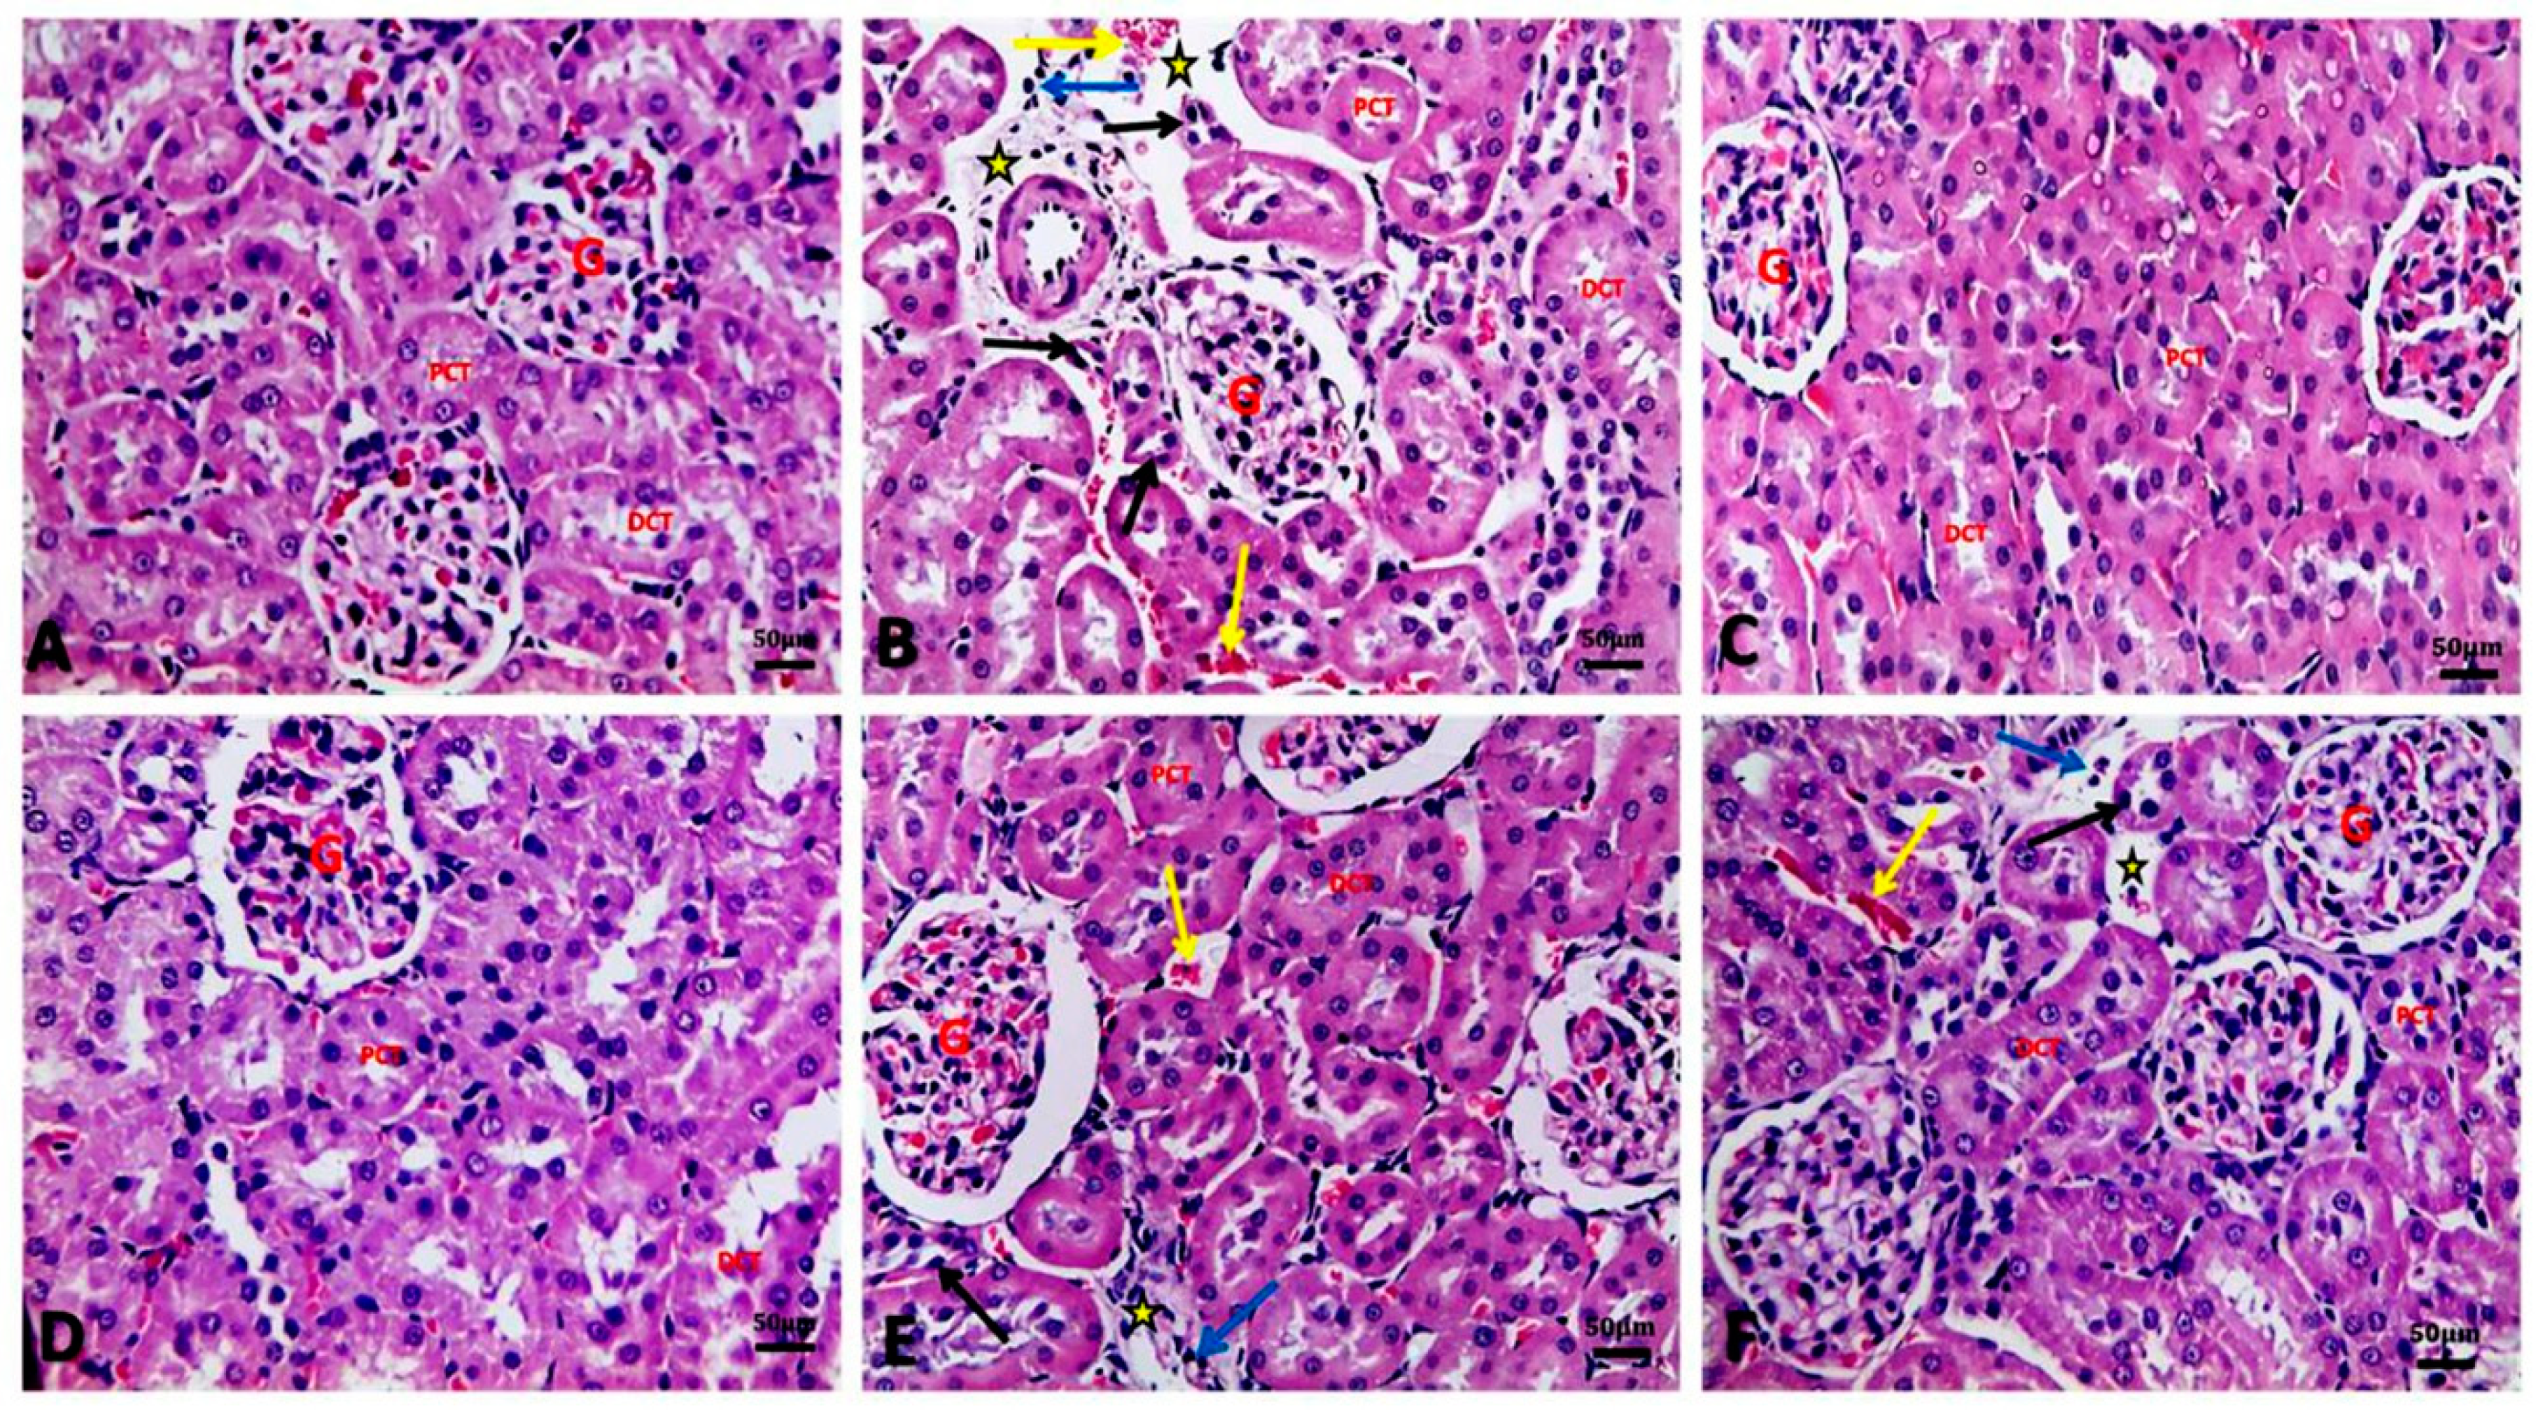

3.6. Argan Oil Ameliorated Betamethasone-Induced Alterations in Renal Histoarchitecture of Rats

Table 4 and Figure 3 illustrated the renal histopathological alterations. Kidneys of the control group showed normal architecture of kidney glomeruli and renal tubules with intact well-organized cellular boundaries (Figure 3A). In contrast, kidney of the BM group showed marked vascular changes, including congestion, and perivascular and interstitial edema associated with degenerative changes as proved by sever atrophy of some proximal convoluted renal tubules with sever nuclear pyknosis, and dilatation of some renal tubules with hyaline and cellular casts. Inflammatory cell infiltration was also seen in renal tissue of the BM group (Figure 3B). Similar to the control group, kidneys of AO/0.5 (Figure 3C) and AO/1 (Figure 3D) groups showed normal architecture of glomeruli and renal tubules. However, administration of AO (0.5 or 1 mL/kg) to BM-treated rats resulted in improvement in renal tissue architecture, except for mild congestion, mild edema, mild nuclear pyknosis of some renal tubular cells, and few inflammatory cell infiltrations in the interstitial tissue (Figure 3E, 3F, respectively).

Figure 3. Representative photomicrographs of histopathological alterations in kidney sections of different groups (H&E stain X20; scale bar 50 μm; star: edema, yellow arrow: congestion, black arrow: tubular atrophy with nuclear pyknosis, blue arrow: inflammatory cell infiltration, G: glomeruli, PCT: proximal convoluted tubules, DCT: distal convoluted tubules). (A) Control group showing normal architecture of kidney glomeruli and renal tubules (proximal and distal convoluted tubules) with intact well organized cellular boundary. (B) BM group showing perivascular edema and congestion in the interstitial tissue in between renal tubules, atrophied proximal renal tubules with nuclear pyknosis, and inflammatory cell infiltration. (C) AO/0.5 and (D) AO/1 showing normal architecture of glomeruli and renal tubules as control group. (E) BM+AO/0.5 group and (F) BM+AO/1 group showing mild congestion, mild edema, and mild nuclear pyknosis of some renal tubular cells and mild inflammatory cell infiltration in the interstitial tissue.